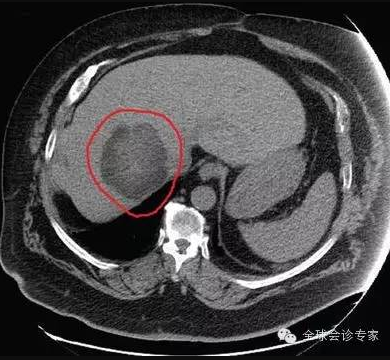

患者,65岁,男,2014年10月腹部不适、头疼检查,诊断为(1)高分化肝细胞癌,大小约250px,明显肝硬化。(2)脑转移瘤,左枕叶处大小约75px。(3)II型糖尿病,需要胰岛素治疗。(4)慢性肾病;(5)中度高血压,有心衰病史。

患者病情处于晚期,体内病灶巨大且有脑转移,不能实施外科手术治疗。经亨利福特医院专家组咨询,患者于2014年11月10日在美国亨利福特医院进行EDGE无创手术治疗。先后对肝脏肿瘤和脑转移瘤进行EDGE治疗,在医院共治疗8天。每个肿瘤每天治疗1次,每次治疗约10分钟左右,肝脏肿瘤共治疗6次,脑肿瘤治疗4次。

患者手术过程中无任何不适,每次治疗后正常回家。2015年5月回访,患者一般情况良好,体重明显增加。经影像检查,肝脏巨大肿瘤被彻底清除,脑部肿瘤几乎完全消除,且没有复发。生化检查,肝功能未见正常。

肝脏肿瘤治疗前250px大小